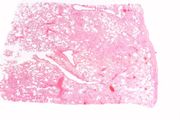

| 16:35, 19 August 2013 | IPLab4Thrombosis2.jpg (file) | 42 KB | Seung Park | This is a low-power photomicrograph of thrombosed coronary artery. The thrombus (1) completely occludes the vessel. Note the layering of the thrombus. The fibrous cap is ruptured (arrow) and there is hemorrhage into the atherosclerotic plaque. Note the... | 1 | |